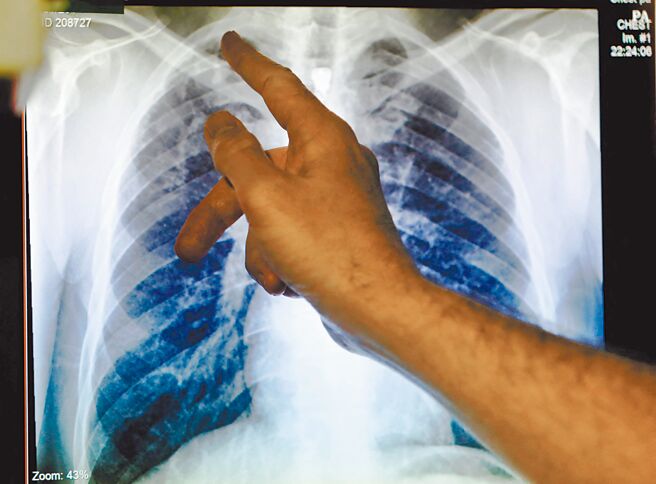

世界衛生組織(WHO)29日指出,2023年全球結核病新增病例達到歷史新高820萬例,較2022年的750萬成長顯著。結核病取代新冠病毒,再度成為全球頭號傳染病殺手,一年內死亡人數幾乎達到愛滋病的兩倍之多。疾管署副署長羅一鈞分析,新冠期間因為封城措施,導致追蹤病患沒有辦法獲得妥善的治療和追蹤,也無法支持結核病的篩檢,是全球失控原因,所幸台未出現這個問題。

這分報告指出,因結核病死亡的人數自2022年的132萬人下降至2023年的125萬人,然而,全球感染人數卻攀升至1080萬人。分析指出,死亡人數持續下降,顯示各國醫療體系已從疫情中逐漸恢復,但去年患有多重耐藥性結核病的40萬人中,接受診斷的人數仍低於半數。

營養不良、愛滋感染、酒精依賴、吸菸和糖尿病等因素是結核病新增數上升的主要推手。結核病主要集中於東南亞、非洲和西太平洋地區,尤其印度、印尼、中國、菲律賓和巴基斯坦5國,占全球整體病例的56%。成年男性患者占55%、女性33%,兒童和青少年則為12%。